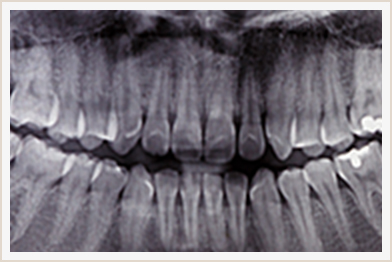

多くの人が経験した事のある虫歯や歯周病。きちんと毎日歯を磨いているのに、なぜまた虫歯になったり、歯周病が悪化したりするのだろう...と疑問に思ったことはありませんか?

- (2) 噛み合わせの問題(=歯のオーバーワーク)

- 噛み合わせが合っていないと強く噛み締めることが多くなるので歯に過大な力がかかり、歯を支えている組織の恒常性維持機構が正しく働かず、虫歯や歯周病、歯の破折の原因になってしまいます。

- ※歯のオーバーワークは目に見えないものなので、詳しく検査して調べる必要があります。

虫歯を繰り返す原因には歯磨き不足だけではなく、噛み合わせのような根深い問題が潜んでいることがほとんどです。まずは検査をして、何が原因で虫歯や歯周病が引き起こされたのかを知る事が大切になります。